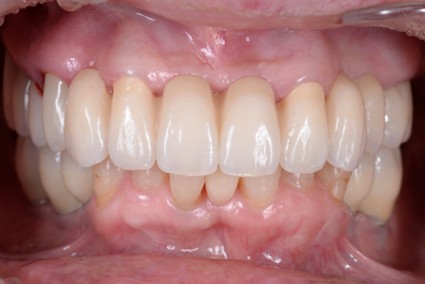

• 治療前

• 治療後